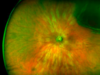

Pathologie rétinienne et injection intravitréennes IVT

Les pathologies rétiniennes sont multiples les plus fréquentes sont la Dégénérescence maculaire lié à l’âge DMLA, les Rétinopathies et Maculopathie diabétique, les maladies vaculaires, les dystrophies héréditaires ainsi que les pathologies infectieuses et inflammatoire.

Aidé par un équipement performant et une solide expérience nos ophtalmologues poserons un diagnostic et proposeront un suivi et traitement adapté. Pour traitements par une salle dédiée permettra la réalisation de ces dernières dans de parfaites conditions.